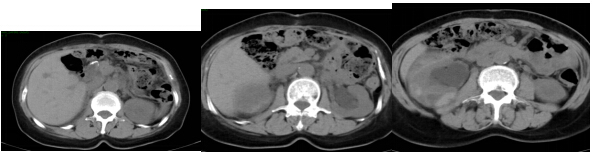

图2 2014年10月,术后第4年的腹部CT

至术后第4年即2014年10月14日,患者主诉腰酸不适、尿量减少、低热、胃纳下降且体重较前明显减轻。肿瘤标志物CEA、CA199、AFP均较前增高。腹部CT示:1.胃癌术后改变:吻合口显示欠清。2.双肾积水,考虑双侧输尿管中下段存在梗阻,原因尚待明确。3.后腹膜及右侧髂血管旁可疑多发肿大淋巴结。PET-CT示:1.胃癌术后腹膜广泛转移,致双侧输尿管中下段梗阻,双肾积水。2.腹主动脉及髂血管旁多发转移淋巴结。